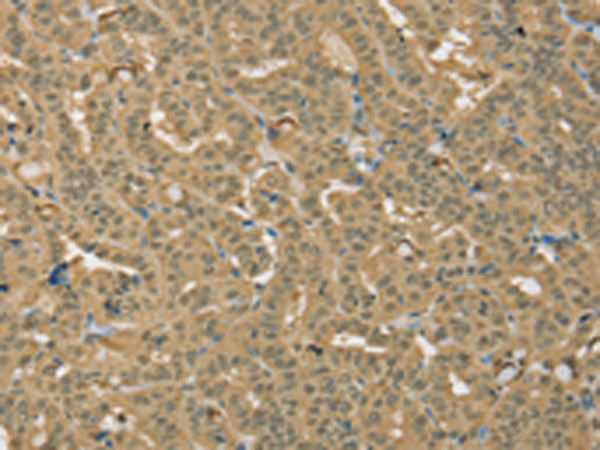

分类: 科研抗体货号: P08618别名: HPH2; PHD2; SM20; ECYT3; HALAH; HPH-2; HIFPH2; ZMYND6; C1orf12; HIF-PH2应用: IHC反应种属: Human, Mouse, Rat